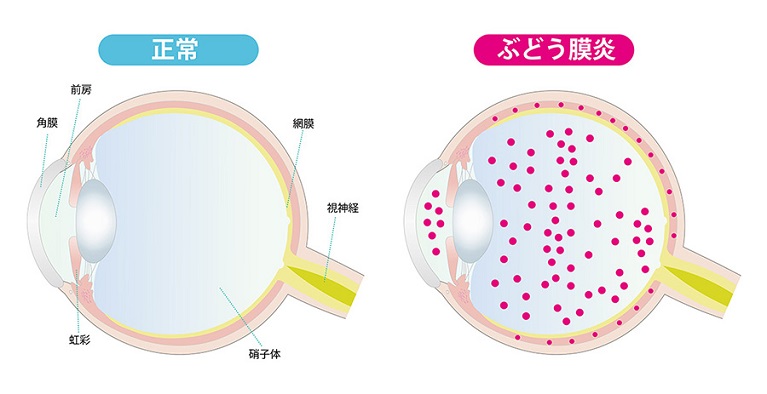

ぶどう膜炎

日本眼科学会画像 引用

サルコイドーシス、原田病、ベーチェット病といった免疫系の疾患、細菌・ウイルスへの感染などを原因として起こる、ぶどう膜の炎症です。炎症は、目の中へと波及していきます。まぶしさの他、目の痛み、視界のぼやけ、飛蚊症などの症状が見られます。